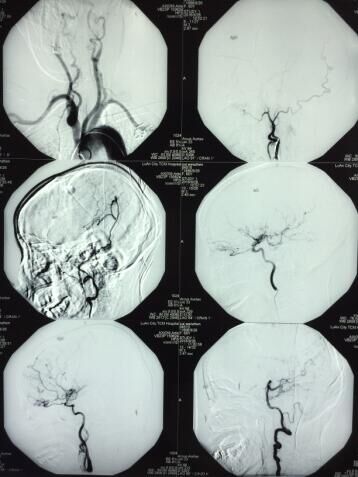

患者 女,60岁;诊断:出血性烟雾病;DSA示“双侧颈内动脉末端闭塞、双侧大脑中动脉、大脑前动脉起始端闭塞;左颈外动脉向颅内供血,右颈外动脉无供血”

经充分术前评估及准备后,于2016.9.30给患者实施“颅内外血管搭桥手术即STA-MCA M4吻合术”。该手术为六安市首例,安徽省仅省立医院、安医附院开展。

手术过程:在麻醉科王大月主任精细麻醉及全程监护下,杜向阳主任和桂明医师在显微镜下,先在头皮下小心分离出颈外动脉的分支-颞浅动脉(STA)额支和顶支,然后仔细剥离颞肌,铣开骨瓣,保留脑膜中动脉完整;剪开硬膜,撕开蛛网膜,选择合适的大脑中动脉(MCA)的M4分支;然后选择较粗的STA额支与M4搭桥、吻合;手术顺利、成功,搭桥血管通畅。